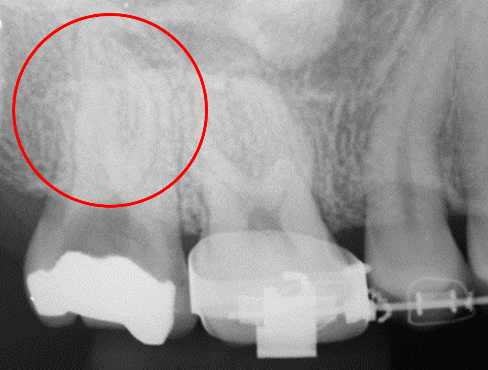

CASE01

抜髄30代 女性

初診時

-

治療後

主訴

右上奥歯が痛い。

治療の概要

虫歯が歯髄に到達していたため、抜髄して根管充填を行いました。

リスクと副作用

コストがかかる。

- 治療費

- 176,000円

- 治療回数

- 2回